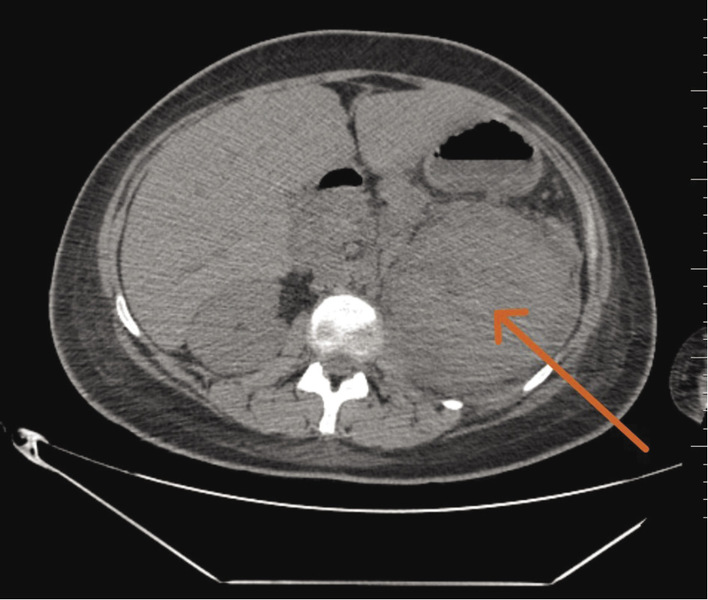

W jednofazowej tomografii komputerowej (TK) lewa nerka okazała się znacznie powiększona (o długości 161 mm), z naciekiem otaczającej tkanki tłuszczowej (ryc. 1). Wysunięto podejrzenie ostrego odmiedniczkowego zapalenia nerek (OOZN). W momencie wykluczenia chirurgicznej etiologii prezentowanych dolegliwości chorą zakwalifikowano do hospitalizacji na oddziale o profilu chorób wewnętrznych.

Rycina 1. Obraz jednofazowej tomografii komputerowej jamy brzusznej – badanie przeprowadzone w ramach szpitalnego oddziału ratunkowego